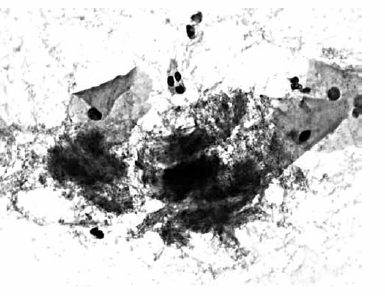

Nas questões de números 46 a 60, assinale a alternativa que melhor corresponde ao diagnóstico do quadro microscópico apresentado.

Alterações celulares benignas reativas; presença de alterações compatíveis com herpesvírus.